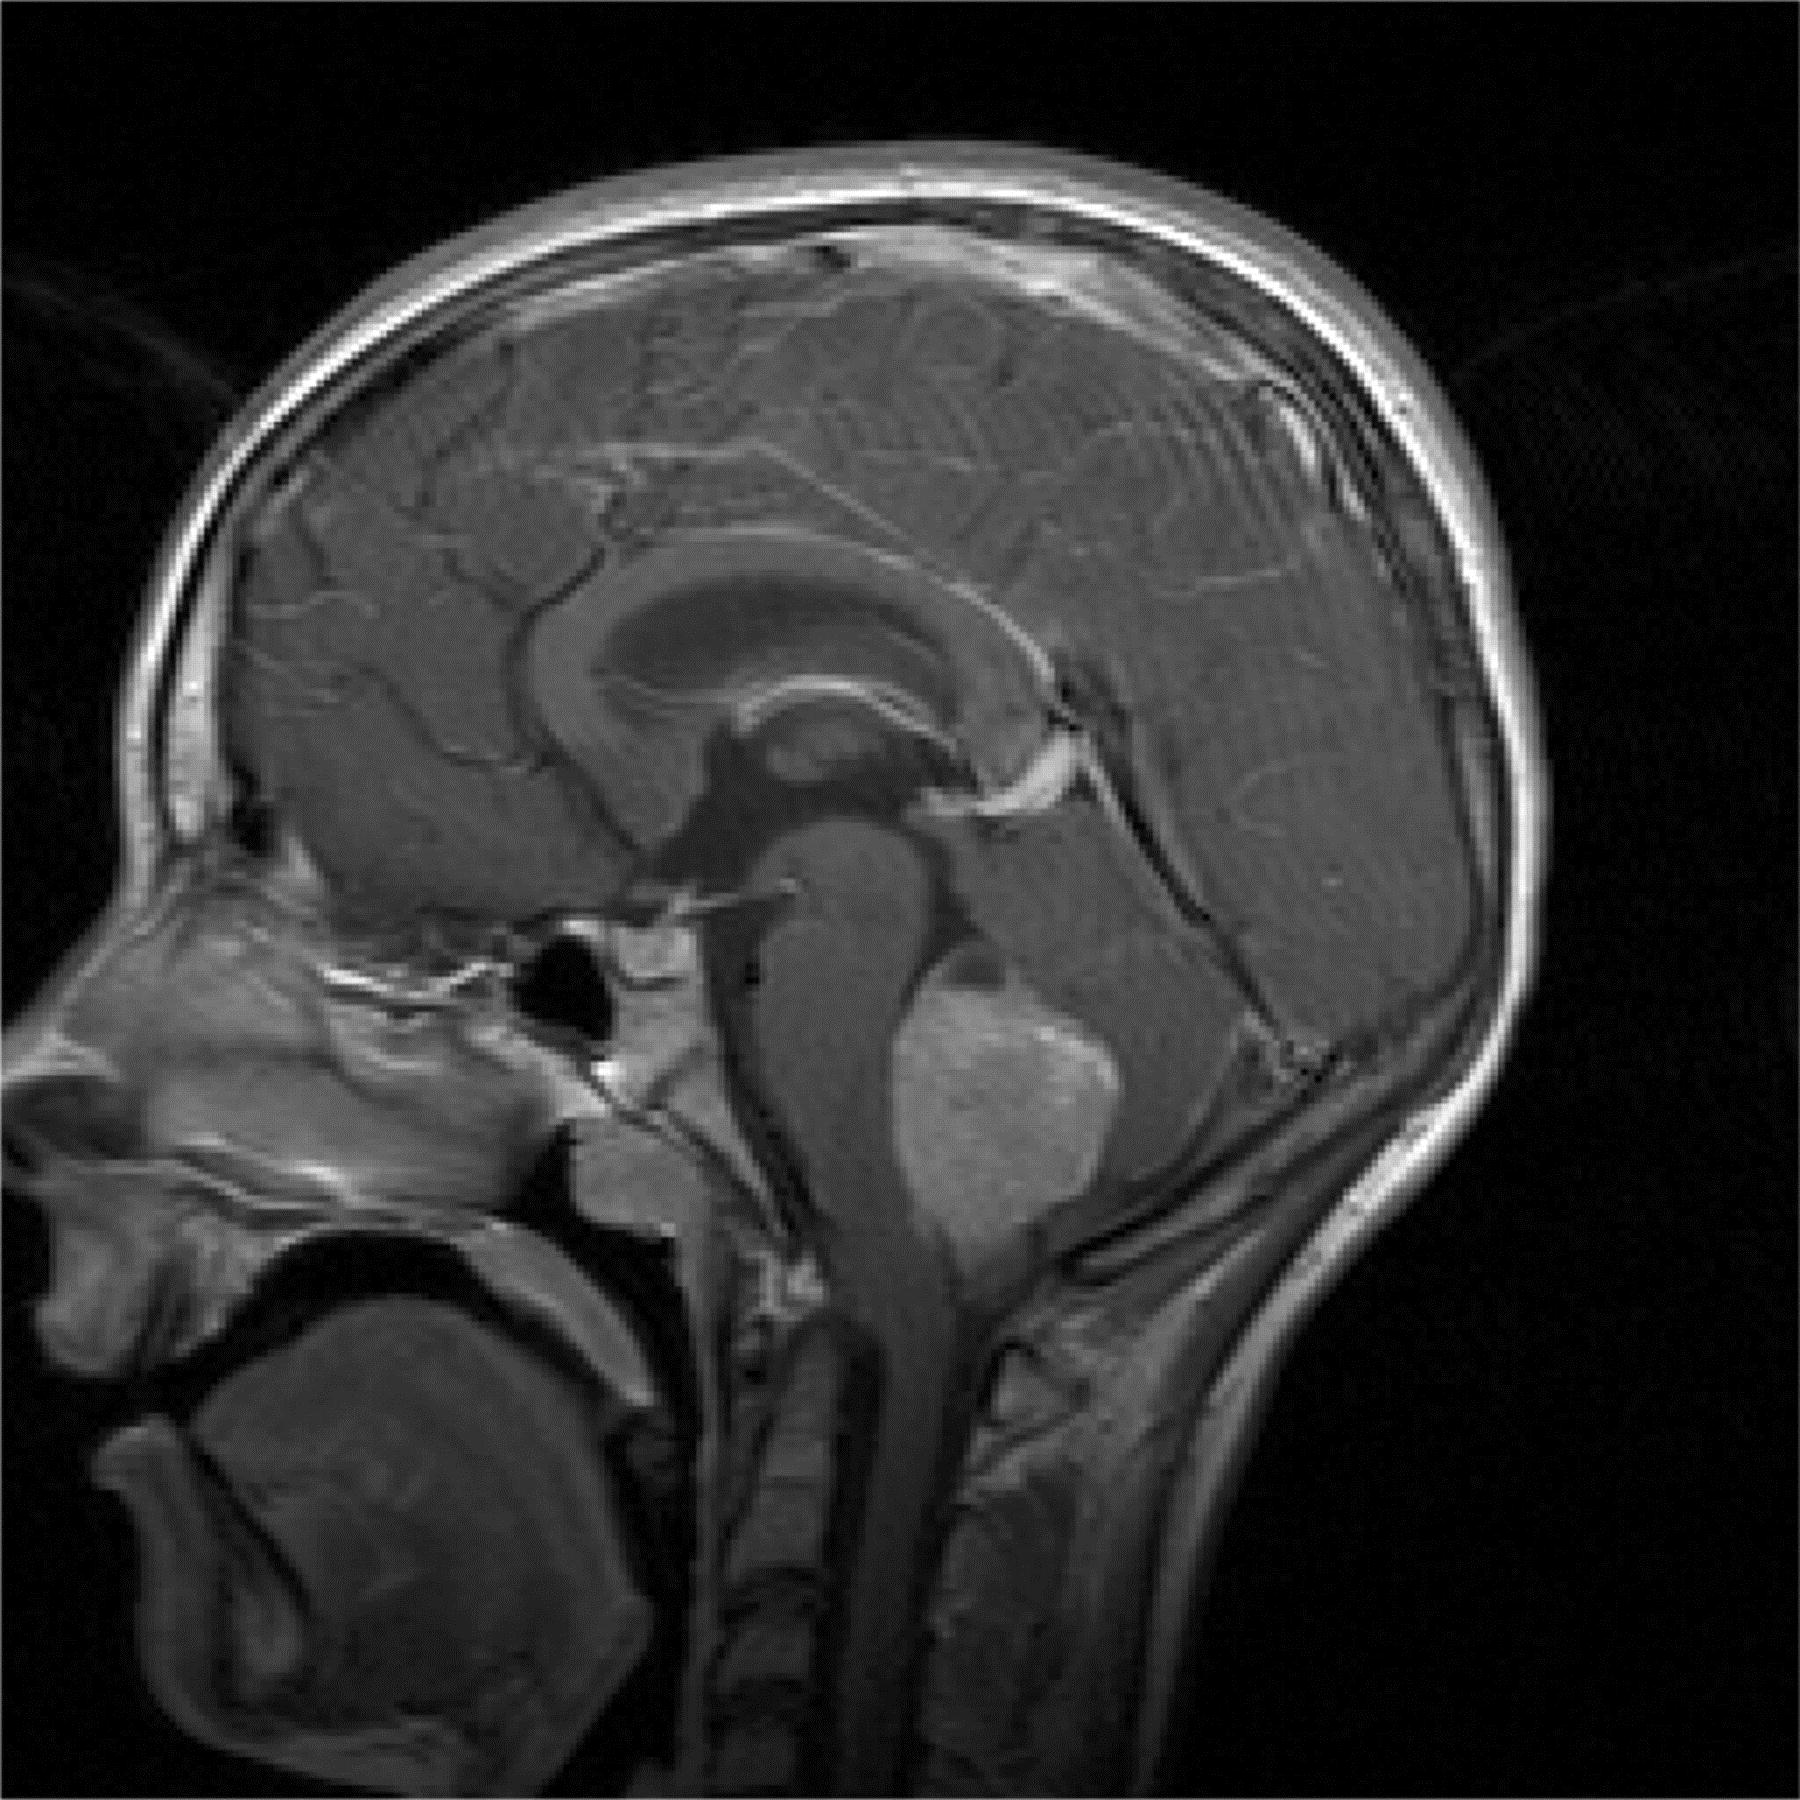

Kui neuroloogilisel uuringul esineb patoloogiline leid või anamneesi alusel tekib ajukasvaja kahtlus, tuleks teostada aju piltdiagnostika: pea kompuutertomograafia või magnetresonantstomograafia - uuringud, mis annavad ülevaate peaajus esinevatest ehituslikest muutustest. Kui nende uuringute alusel on kahtlus kasvajale, siis neurokirurg operatiivsel teel eemaldab kasvaja kas täielikult või osaliselt ja patoloog annab histoloogilise vastuse. Haiguse ulatuse hindamiseks vajalik ka seljaajuvedeliku ehk liikvori uuring.

Madalmaliigsed glioomid moodustavad 40% lapseea ajukasvajatest. Glioome iseloomustatakse täiendavalt selle alusel, mis tüüpi rakke nad haaravad: astrotsütoom lähtub tähekujulistest gliiarakkudest, mida kutsutakse astrotsüütideks. Kõige sagedasem alatüüp on pilotsüütastrotsütoom, mis on aeglase kasvuga. Kõige tavalisem vanuses 3-14.aastat. Sagedaseim pahaloomuline kasvaja lastel on medulloblastoom, moodustades 20% ajukasvajatest. See kasvaja lähtub tavaliselt väikeajust. Keskmise vanus diagnoosimisel on 5.- 9. aastat. Peale operatsiooni jaotatakse haiged riskigruppidesse.

Ependümoom lähtub rakkudest, mis vooderdavad vatsakesi või seljaaju keskkanalit, moodustades 10% ajukasvajatest. Keskmine vanus diagnoosimisel esimesed neli eluaastat.